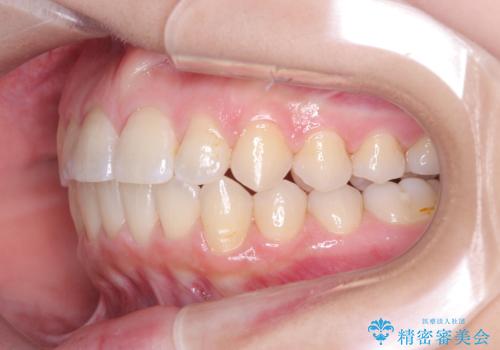

右下第二小臼歯の舌側転移の改善

- 患者様は、右下第二小臼歯が舌側に転移していることが主訴でした。診断の結果、抜歯を伴う矯正治療も検討しましたが、奥歯の遠心移動とIPR(インタープロキシマルリダクション)を行うことで、非抜歯で矯正を進めることが可能であると判断しました。治療計画では、審美ワイヤーを用いた2年間の治療で、歯列を整えつつ、臼歯関係や正中のバランスを維持しながら進めました。

非抜歯矯正では、歯の動きを慎重に調整することが求められます。本症例では、奥歯を遠心に移動させることで、舌側に転移した右下第二小臼歯の位置を改善しました。また、IPRを行うことで歯間スペースを確保し、無理なく歯列の調整を行いました。非抜歯での治療は、特に臼歯関係や正中を保ちながら治療できるというメリットがあり、最終的にはバランスの取れた歯並びを実現できました。審美ワイヤーを使用したことで、治療中も目立ちにくく、患者様の見た目にも配慮した治療を行いました。